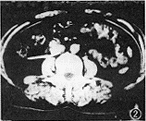

患者 女,37岁。反复发作腰痛半年,B超诊为右肾积水入院。静脉尿路造影除显示右肾盂积水外,还可见右肾盂、输尿管移行部明显扩张,在第3、4腰椎水平,输尿管陡然变窄,呈鱼钩状,尖端指向上、内方,中、下段输尿管不显影(图1)。经膀胱镜向右侧输尿管插入输尿管导管,注入60%泛影葡胺,行逆行尿路造影,可见右肾盂积水和上段输尿管扩张,但仍不能显示中、下段输尿管的走行以及输尿管周围的毗邻关系。保留导管再注入泛影葡胺5ml,行肾脏、输尿管CT扫描(层厚10 mm),CT显示右侧输尿管绕行于下腔静脉后方(图2);矢状面重建,显示输尿管先位于下腔静脉后,而后又绕到下腔静脉前方(图3)。诊断为下腔静脉后输尿管。手术见右肾外观及皮质厚度正常,肾盂中度积水,上段输尿管明显扩张,迂曲成角,经腰大肌边缘变细并绕行下腔静脉后方(图4)。将近端扩张部输尿管切断,将输尿管游离至下腔静脉前方,行对端吻合。出院后3个月,症状消失,B超复查,肾盂积水消失。

图1 静脉尿路造影,示肾盂积水,肾盂与上端输尿管扩张,呈鱼钩状 图2 逆行尿路造影CT扫描横断面图像,示输尿管伸向下腔静脉后方 图3 矢状面重建图像,示输尿管先位于下腔静脉后,再绕至前方 图4 手术见输尿管在腰大肌前方绕向下腔静脉后,再穿至前方

CT平扫能显示下腔静脉,但输尿管不易辨认。增强CT可使肾盂、输尿管显影,可以明确输尿管与下腔静脉的位置关系,能对本病做出诊断[2] 。应用逆行尿路造影结合CT扫描,可清楚看到输尿管在腰大肌前方、下腔静脉后方绕行;矢状面重建显示输尿管先位于下腔静脉后方、脊柱前方,即输尿管的下腔静脉后段,而后又绕到下腔静脉前方,使本病在手术前即可明确诊断。本方法经输尿管导管直接注药,对肾功能无依赖,对于因重度肾积水所致肾功能减退、静脉尿路造影或增强CT肾盂、输尿管不显影者,更为适宜。